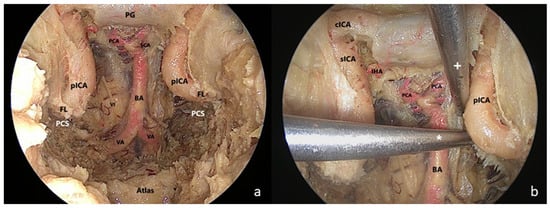

2.2. Surgical Technique

- The clival step

- The petrosal step